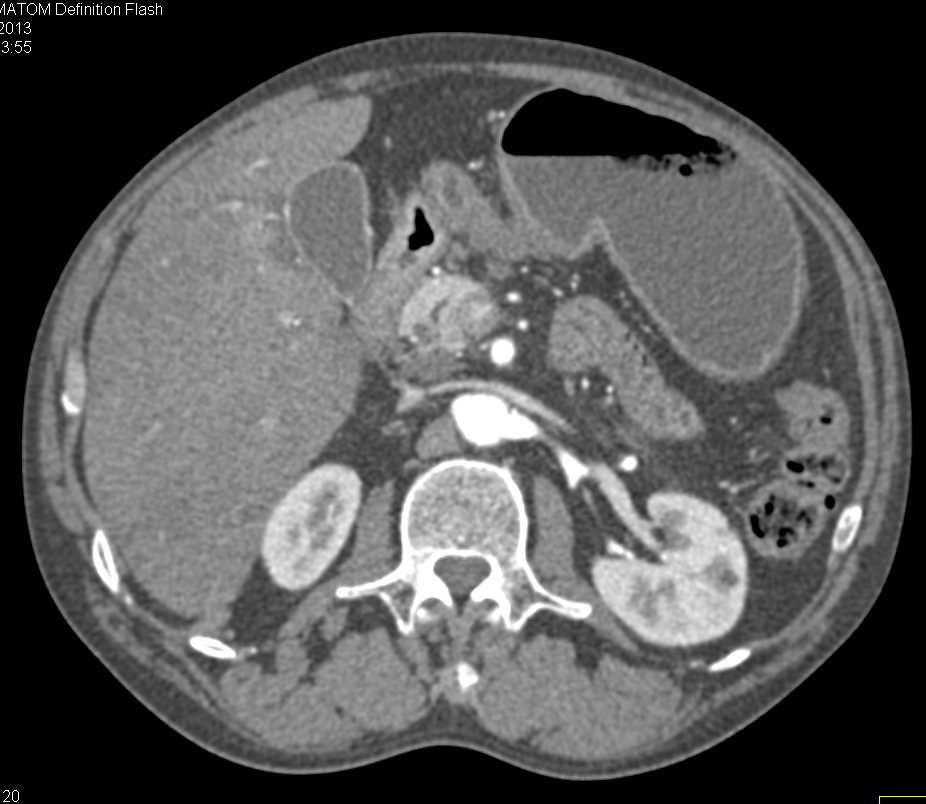

Carcinoma of the 3rd Portion of the Duodenum